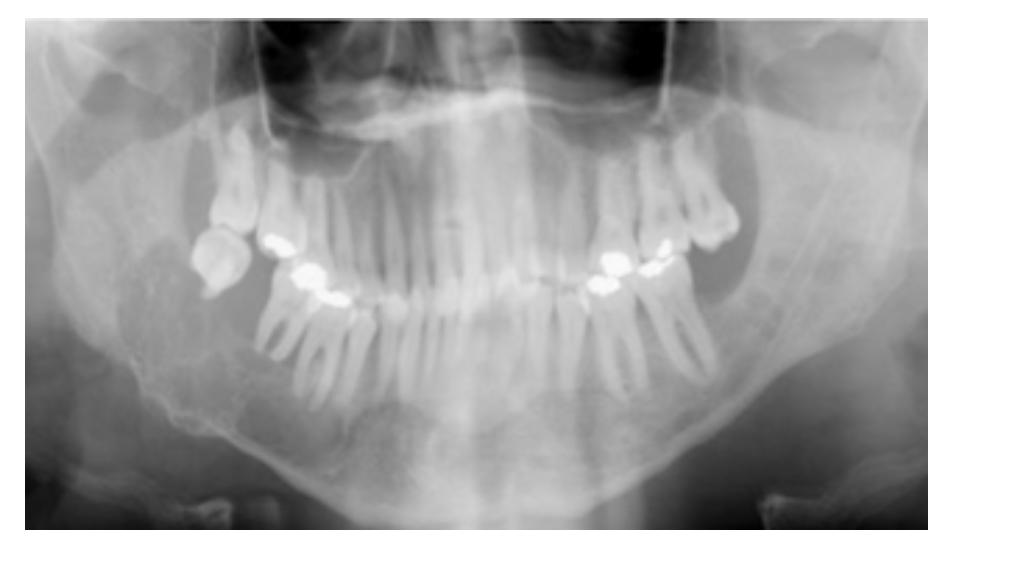

Punched out “Ice cream scoop” radiolucencies

* lead to floating teeth